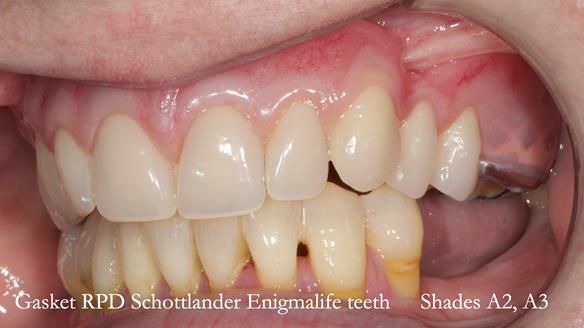

Welcome to my Newsletter 58, where I show the making and fitting of an upper gasket partial denture for Zoe (52 year old woman). This issue provides a comprehensive overview of the entire protocol workflow for this superbly retained denture.

Zoe was referred to me for specialist prosthodontics by her general dentist, after unsuccessful attempts to provide a denture because of fractures, looseness and discomfort.

The detailed clinical situation and treatment process are outlined below, with clinical work provided by me and technical work by Rowan Garstang. The treatment spanned five visits for denture fitting and one review.